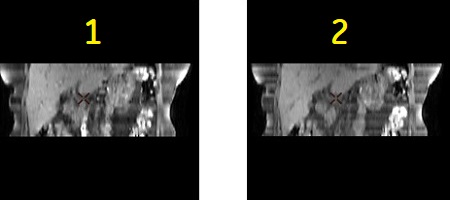

In-flow artifact

T1-weighted images normally have a dark vessel signal due to saturation effects. This vessel signal can be clinically confusing in regions that have a short T1. The vessel signal becomes bright due to an in-flow effect around the edge slices or in 2D multiple acquisitions with an interleaved slice order.

To suppress signal from slow flow, apply the In-flow signal reduction with 2D FSPGR or 2D Dual Echo and thus minimize the artifact.

| Number | Description |

|---|---|

| 1 | 2D FSPGR acquired with In-flow signal reduction User CV set to OFF (=0). |

| 2 | 2D FSPGR acquired with In-flow signal reduction User CV set to ON (=1). |